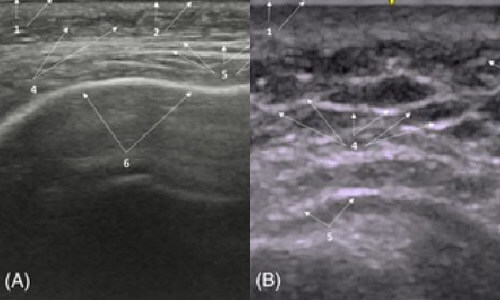

在正常的情況下,表皮與真皮在超音波影像上呈現一條連續亮白線,表示皮膚健康完整。

脂肪層在超音波影像上看起來黑灰交錯像蜂巢,中間很多細白線,那些白線叫 FSN(纖維隔網),就像彈力網一般支撐臉。 這樣的結構代表皮膚和脂肪鬆軟、有彈性,表情、血流、光澤都靠它。

🔔 臨床判斷:如果看到脂肪層中有那些過亮的的區塊,其實就是暗示那個位置有異物反應造成的纖維化